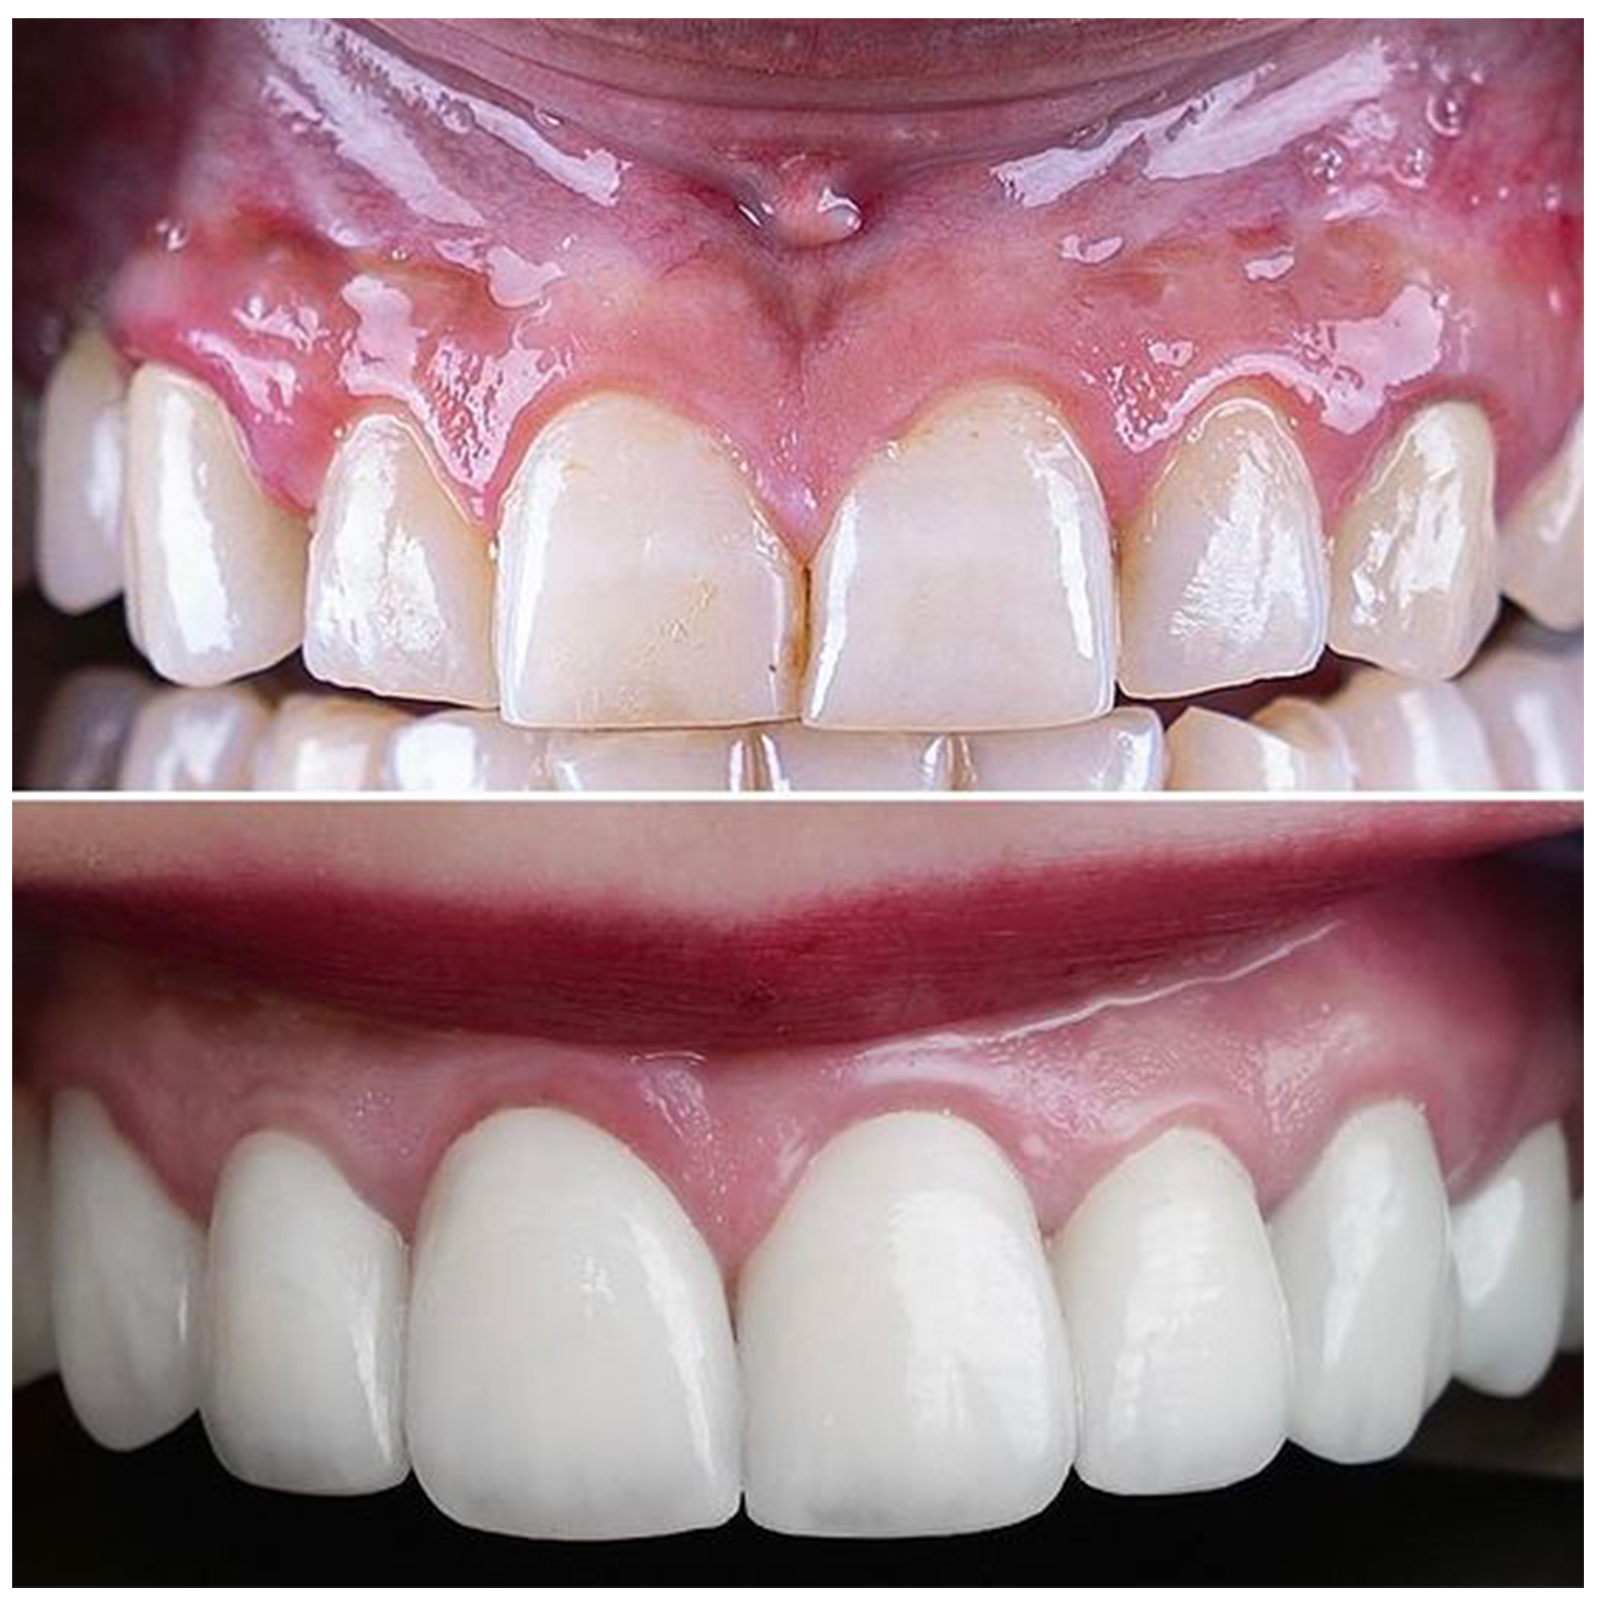

Dr. PRASHANTHY.R.BDS, MDS, FICOI,DICOIPeriodontist / Implantologist-Board certified Diplomate (ICOI )Healthy Gums and Teeth for a Beautiful Smile

Specialist inPeriodontist

Specialist inImplantology